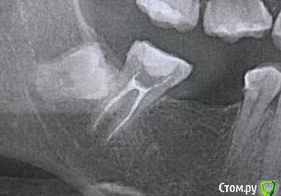

nataganka Опубликовано 9 декабря, 2019 Автор Поделиться Опубликовано 9 декабря, 2019 Нет, ну я точно перешла дорогу какой-то зубной феечке, у меня уже смех истерический))))) ладно бы гигиену не соблюдала, но нет ведь, и нитью пользуюсь после еды, и ирригатором пользуюсь и щетка электрическая))))))) видимо и впрямь наследственность такая штука коварная. В общем, не успела я заняться удалением ретинированного 48-го зуба... так как теперь финансы потекли в зуб 27. И полугода не прошло. У меня там была пятилетней давности пломба, которая не вызывала ни у кого вопросов собственно на осмотрах и лечении зубов все начало этого года. В ноябре откололся кусочек пломбы, при том ела обычную пищу, не твердую. Под ней внутри зуба оказалась кариозная полость и довольно таки обширная, глазом пока пломба не откололась ее не было видно ни одному врачу, коих я посетила за этот год множество (( Так вот теперь предстоит лечение, либо обойдется пломбой, либо снова депульпация и коронка с вкладкой. По снимку врачи сказали, что на грани, все станет ясно на лечении. Как мне снять карму со своих зубов, чтобы денег хватало на жизнь и одежду, а не относила все финансы в стоматологию? Вопрос походу риторический))))))))))А теперь вопрос фактический, если все-таки будут депульпировать, то можно ли потом это все закрыть керамической реставрацией, а не вкладку+коронку? Сфоткать во рту у меня не получится, по причине расположения зуба. Снимок с предыдущей страницы. Зуб и кариозная полость отмечена Ссылка на комментарий